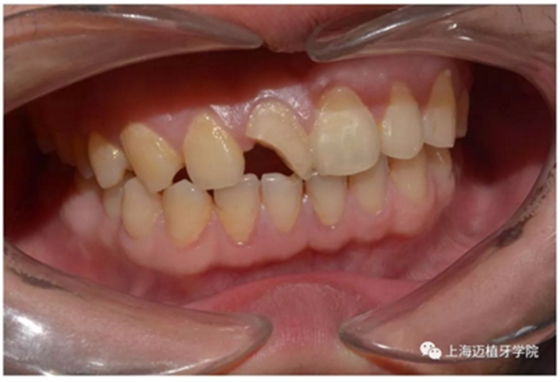

主訴:前門外傷牙根折要求修復(fù)?現(xiàn)病史:前門牙外傷,劈裂至根部,無法固定及其他修復(fù),要求種植?檢查:11牙冠2/3缺損,唇腭向劈裂,唇部紅腫。 CT示根折, 骨寬度9.47mm,距鼻底12.34mm,Ⅲ類骨。 口腔衛(wèi)生一般

術(shù)前照片